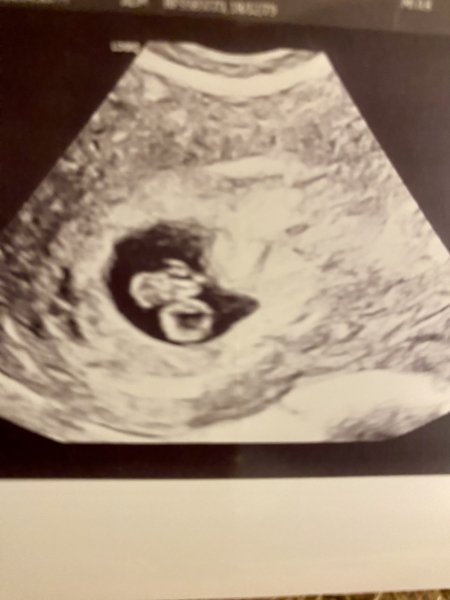

Hi! For those with no symptoms please try not to worry, I've had my first scan today 6+4 and there's a little sticky bean baby with a strong little heartbeat, I was so sure they were going to tell me it wasn't a viable pregnancy due to lack of symptoms. We're just lucky she said and to make the most of feeling so well in this early stage that can be so hard for others. Baby is the right horn of my stupid weird uterus but in a safe position and she gave me a due date of 01/09/24 which is our prediction too.

The baby is on top of the yolk sac (the bottom bubble) 7.5mm at this stage!!

@MudandMoet What a beautiful scan picture! Congratulations! 😍

@MudandMoet what a lovely picture!! How exciting!